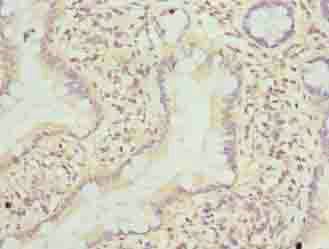

IHC (Immunohistochemistry)

(Immunohistochemistry of paraffin-embedded human colon cancer using AAA230072 at dilution of 1:100)